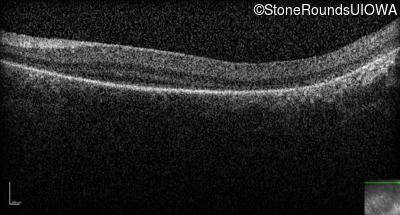

Optical Coherence Tomography - Left -

No Light Perception

Exemplar

Expanded OCT Stack

×